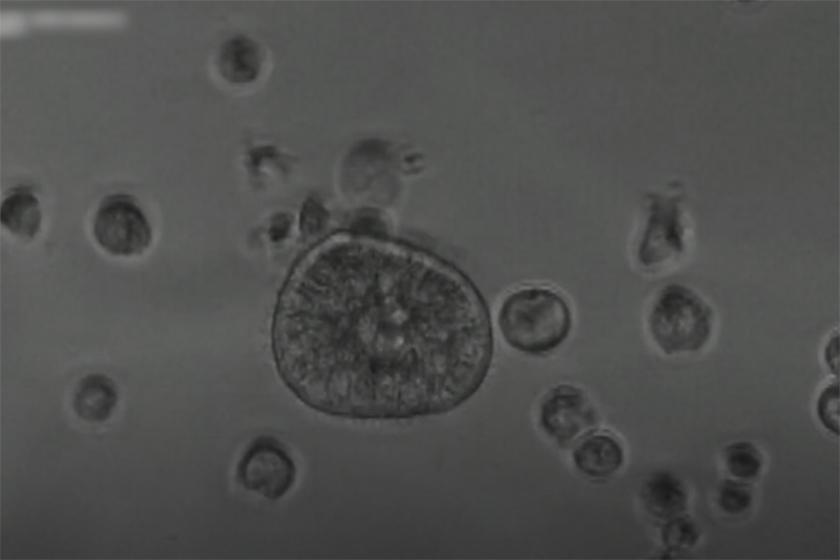

خبرگزاری ایسنا نوشت: پژوهشگران دو دانشگاه هاروارد و تافتس موفق شدند با استفاده از سلولهای بیماران، رباتهای بسیار کوچک بیولوژیک به نام «آنثربات» طراحی کنند؛ این رباتها میتوانند به درمان بیماریهای زیادی کمک کنند.